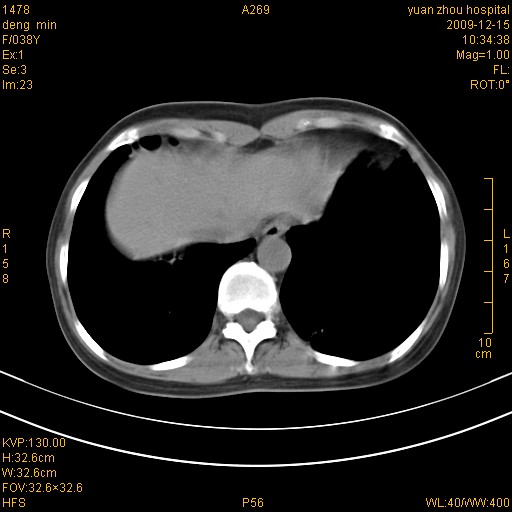

右肺中下叶、左肺上叶舌段及左肺下叶支气管扩张合并感染。